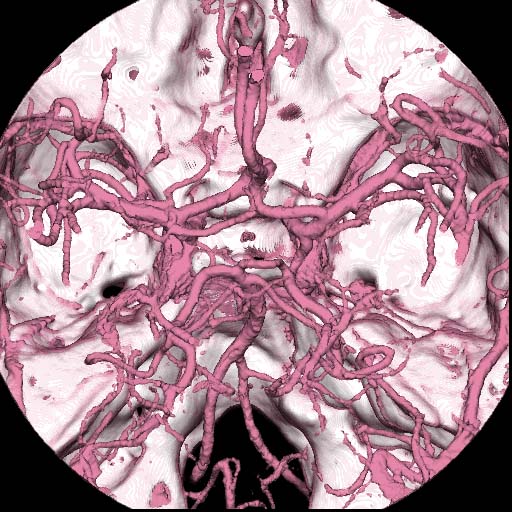

One of the serious shortcomings in thinner slice scanning is a limited scanning range - the thinner the slice is, the gerater is the scanning time required to cover the target organ(s). Two rows of 0.5-mm detector array will only works for the scanning of small organ such as middle ear. On the contrary, orbita, circle of Willis, facial bone, entire skull and brain or even the cervical and lumber spine are accessible to a 4-row system.